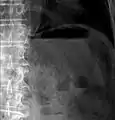

استرواح الأمعاء تحت التصوير المقطعي المحوسب أثناء نقص التروية المعوية. نافذة الرئة لتمثيل أفضل لرواسب الغاز في جدران الأمعاء. إعادة البناء الإكليلي.

استرواح الأمعاء في التصوير المقطعي المحوسب أثناء نقص التروية المعوي. نافذة الرئة لتمثيل أفضل لرواسب الغاز في جدران الأمعاء.